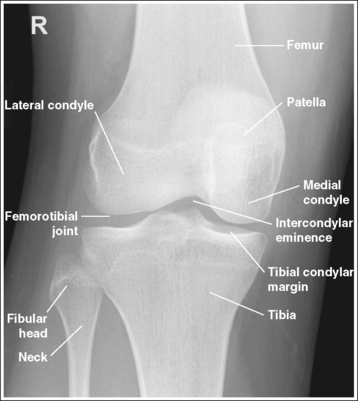

The knee demonstrates an AP projection. The medial and lateral femoral epicondyles are in profile, the femoral condyles are symmetrical, the intercondylar eminence is centered within the intercondylar fossa, and the tibia is superimposed over 0.25 inch (0.6 cm) of the fibular head.

• To obtain an AP knee projection, place the patient in a supine position with the knee fully extended. Internally rotate the leg until an imaginary line drawn between the medial and lateral femoral epicondyles is positioned parallel with the IR (Figure 6-71). This positioning places the medial and lateral femoral epicondyles at equal distances from the IR as well as medially and laterally in profile, respectively. It also centers the intercondylar eminence within the intercondylar fossa and draws the fibular neck and a portion of the fibular head from beneath the tibia.

• Effect of rotation. If the femoral epicondyles are not positioned parallel with the IR, an AP projection has not been obtained. If the patient's leg was not internally rotated enough to place the epicondyles at equal distances from the IR, they are not in profile, the medial femoral condyle appears larger than the lateral condyle, and the tibia is superimposed over more than 0.25 inch (0.6 cm) of the fibular head (see Image 54). If the patient's leg was internally rotated more than needed to place the femoral epicondyles at equal distances from the IR, the epicondyles are not demonstrated in profile, the lateral femoral condyle appears larger than the medial condyle, and the tibia is superimposed over less than 0.25 inch (0.6 cm) of the fibular head (see Image 55).

The knee joint space is open, the anterior and posterior condylar margins of the tibia are superimposed, the intercondylar eminence and tubercles are demonstrated in profile, and the fibular head is demonstrated approximately 0.5 inch (1.25 cm) distal to the tibial plateau.

• The anterior and posterior condylar margins of the tibia are superimposed if the correct central ray angulation, as determined by the patient's upper thigh and buttocks thickness, is used. By studying the tibial plateau region, you will see that the tibial plateau slopes distally approximately 5 degrees from the anterior condylar margin to the posterior condylar margin on both the medial and lateral aspects (Figure 6-72). Only if the central ray is aligned parallel with the tibial plateau slope is an open knee joint space obtained.